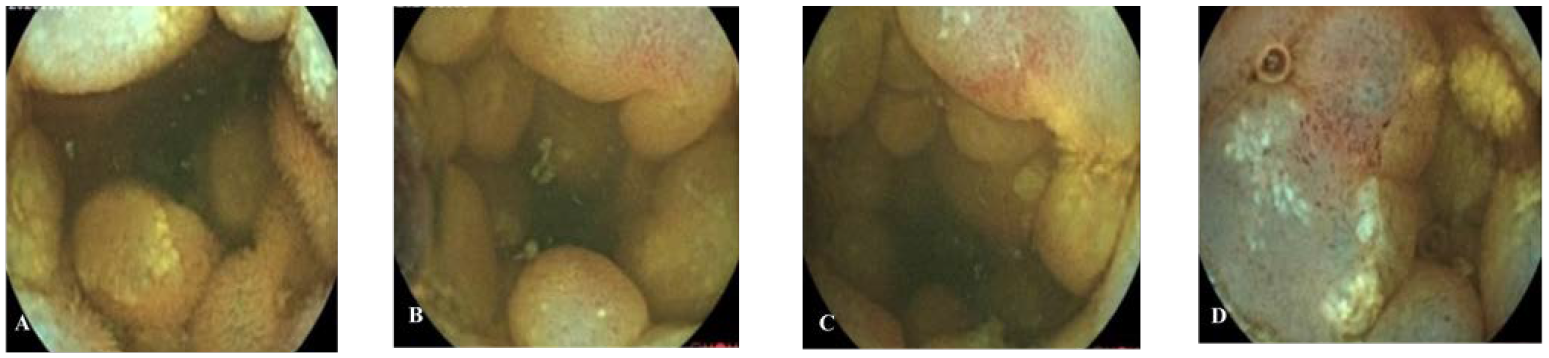

Patient B, a 52-year-old woman, went to the hospital on 3 November 2020 because of “recurrent upper abdominal pain for more than 20 days”. The patient had abdominal pain more than 20 days ago. The pain was mainly in the middle and upper abdomen, which was like a paroxysmal knife cutting and relieved after several seconds. There was no radiating pain in the waist and back, no abdominal distension, and no nausea and vomiting. Physical examination showed tenderness in the middle and right upper abdomen without rebound pain and muscle tension. The abdomen is flat without gastrointestinal type or peristalsis wave, there was no obvious mass, and the bowel sounds are normal. Admission diagnosis revealed abdominal pain of unknown origin. There were no abnormalities in blood routine, CRP, biochemistry, AFP, CA19-9, and CEA. Abdominal enhanced CT showed local intestinal wall edema, structural disorder, and mesenteric edema, as shown in Figure 4. Esophagogastroduodenoscopy revealed bile retention fluid in the stomach. Capsule endoscopy showed ileal lesions, with multiple continuous nodular changes in the mucous membrane, and the surface was red and erosive, as shown in Figure 5. Contrast-enhanced CT of the small intestine showed segmental intestinal wall thickening in the terminal ileum with obvious edema of the surrounding mesentery, which suggested the possibility of inflammatory bowel disease (IBD). CT three-dimensional reconstruction of small intestine showed segmental intestinal wall thickening in the distal ileum with obvious edema in the surrounding mesangium. After consultation with the imaging department, the patient was suspected to have Crohn’s disease (CD) due to the ileal lesions. However, the clinical features and course of the patient did not conform to the typical manifestations of CD, so surgical treatment was important for diagnosis and treatment. The patient underwent surgical treatment on 1 December 2020. Intraoperative exploration revealed a 30-cm-long part of the small intestine with obvious edema and thickening 4.5 m away from the ligament of Treitz. The intestinal lumen was narrow and the mesangial surface was uneven, showing cystic jelly-like changes. During operation, the operator dissected a piece of intestine with a length of 38 cm and a diameter of 4–7 cm. There is an 11 cm × 7 cm mucous bulbous area 6.5 cm away from the cut end on one side and 15 cm from the cut end on the other side. The mesenteric surface was hard in texture, and the cut surface was spongy and gray yellow, as shown in Figure 6. Pathology indicated small intestinal lymphangioma, and no cancer involved both ends, as shown in Figure 3. After the operation, she left the hospital after receiving anti-inflammatory and nutritional support therapy.

Figure 5 Capsule endoscopy of patient B. (A–D) The lesion mucosa showed continuous multiple nodular protrusions, with redness and erosion on the surface.